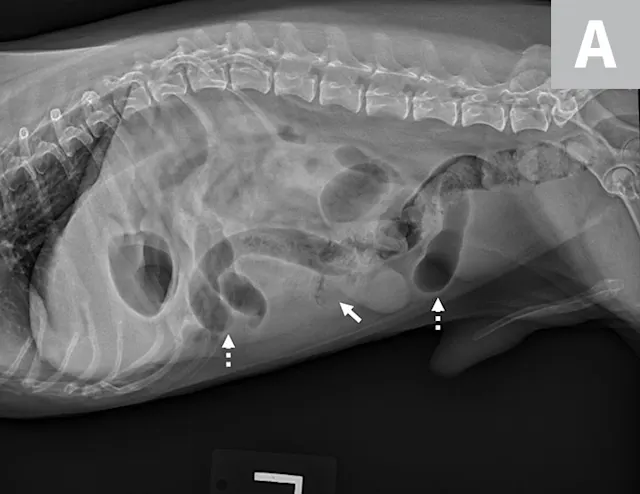

Left lateral image showing segmental dilated gas-filled intestines (dashed arrows) with heterogeneous soft tissue in a small intestinal segment (solid arrow) in a dog. The foreign material was cloth, and the diagnosis was small intestinal mechanical obstruction. Exploratory laparotomy was performed.